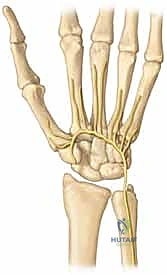

لفهم طبيعة هذه الإصابة، يجب علينا أولاً الغوص في التشريح الدقيق لليد. تتكون اليد من ثلاثة أجزاء عظمية رئيسية:

1. عظام الرسغ (Carpal Bones): وهي 8 عظام صغيرة تشكل قاعدة اليد.

2. عظام المشط (Metacarpal Bones): وهي 5 عظام طويلة تشكل كف اليد.

3. السلّاميات (Phalanges): وهي عظام الأصابع.

مفصل الكربوميتاكاربال هو النقطة التي تلتقي فيها عظام المشط بعظام الرسغ. هذا المفصل ليس متماثلاً في جميع الأصابع:

* المفصل الثاني والثالث (السبابة والوسطى): هي مفاصل صلبة جداً وثابتة، وتعمل كعمود فقري مركزي لليد. حركتها تكاد تكون معدومة لتوفير القوة القصوى أثناء الإمساك بالأشياء.

* المفصل الرابع والخامس (البنصر والخنصر): هي مفاصل أكثر مرونة وتسمح بحركة تتراوح بين 15 إلى 30 درجة. هذه المرونة ضرورية لتشكيل قبضة اليد والقدرة على الإمساك بالأشياء الدائرية أو الأسطوانية.

عند حدوث قوة ضغط هائلة أو التواء شديد، تفشل الأربطة القوية التي تربط هذه العظام، مما يؤدي إلى خلع المفصل. وإذا كانت القوة كافية، فإنها تكسر حافة العظم أثناء خلع المفصل، وهو ما يُعرف بـ كسر وخلع الكربوميتاكاربال (Fracture-Dislocation).